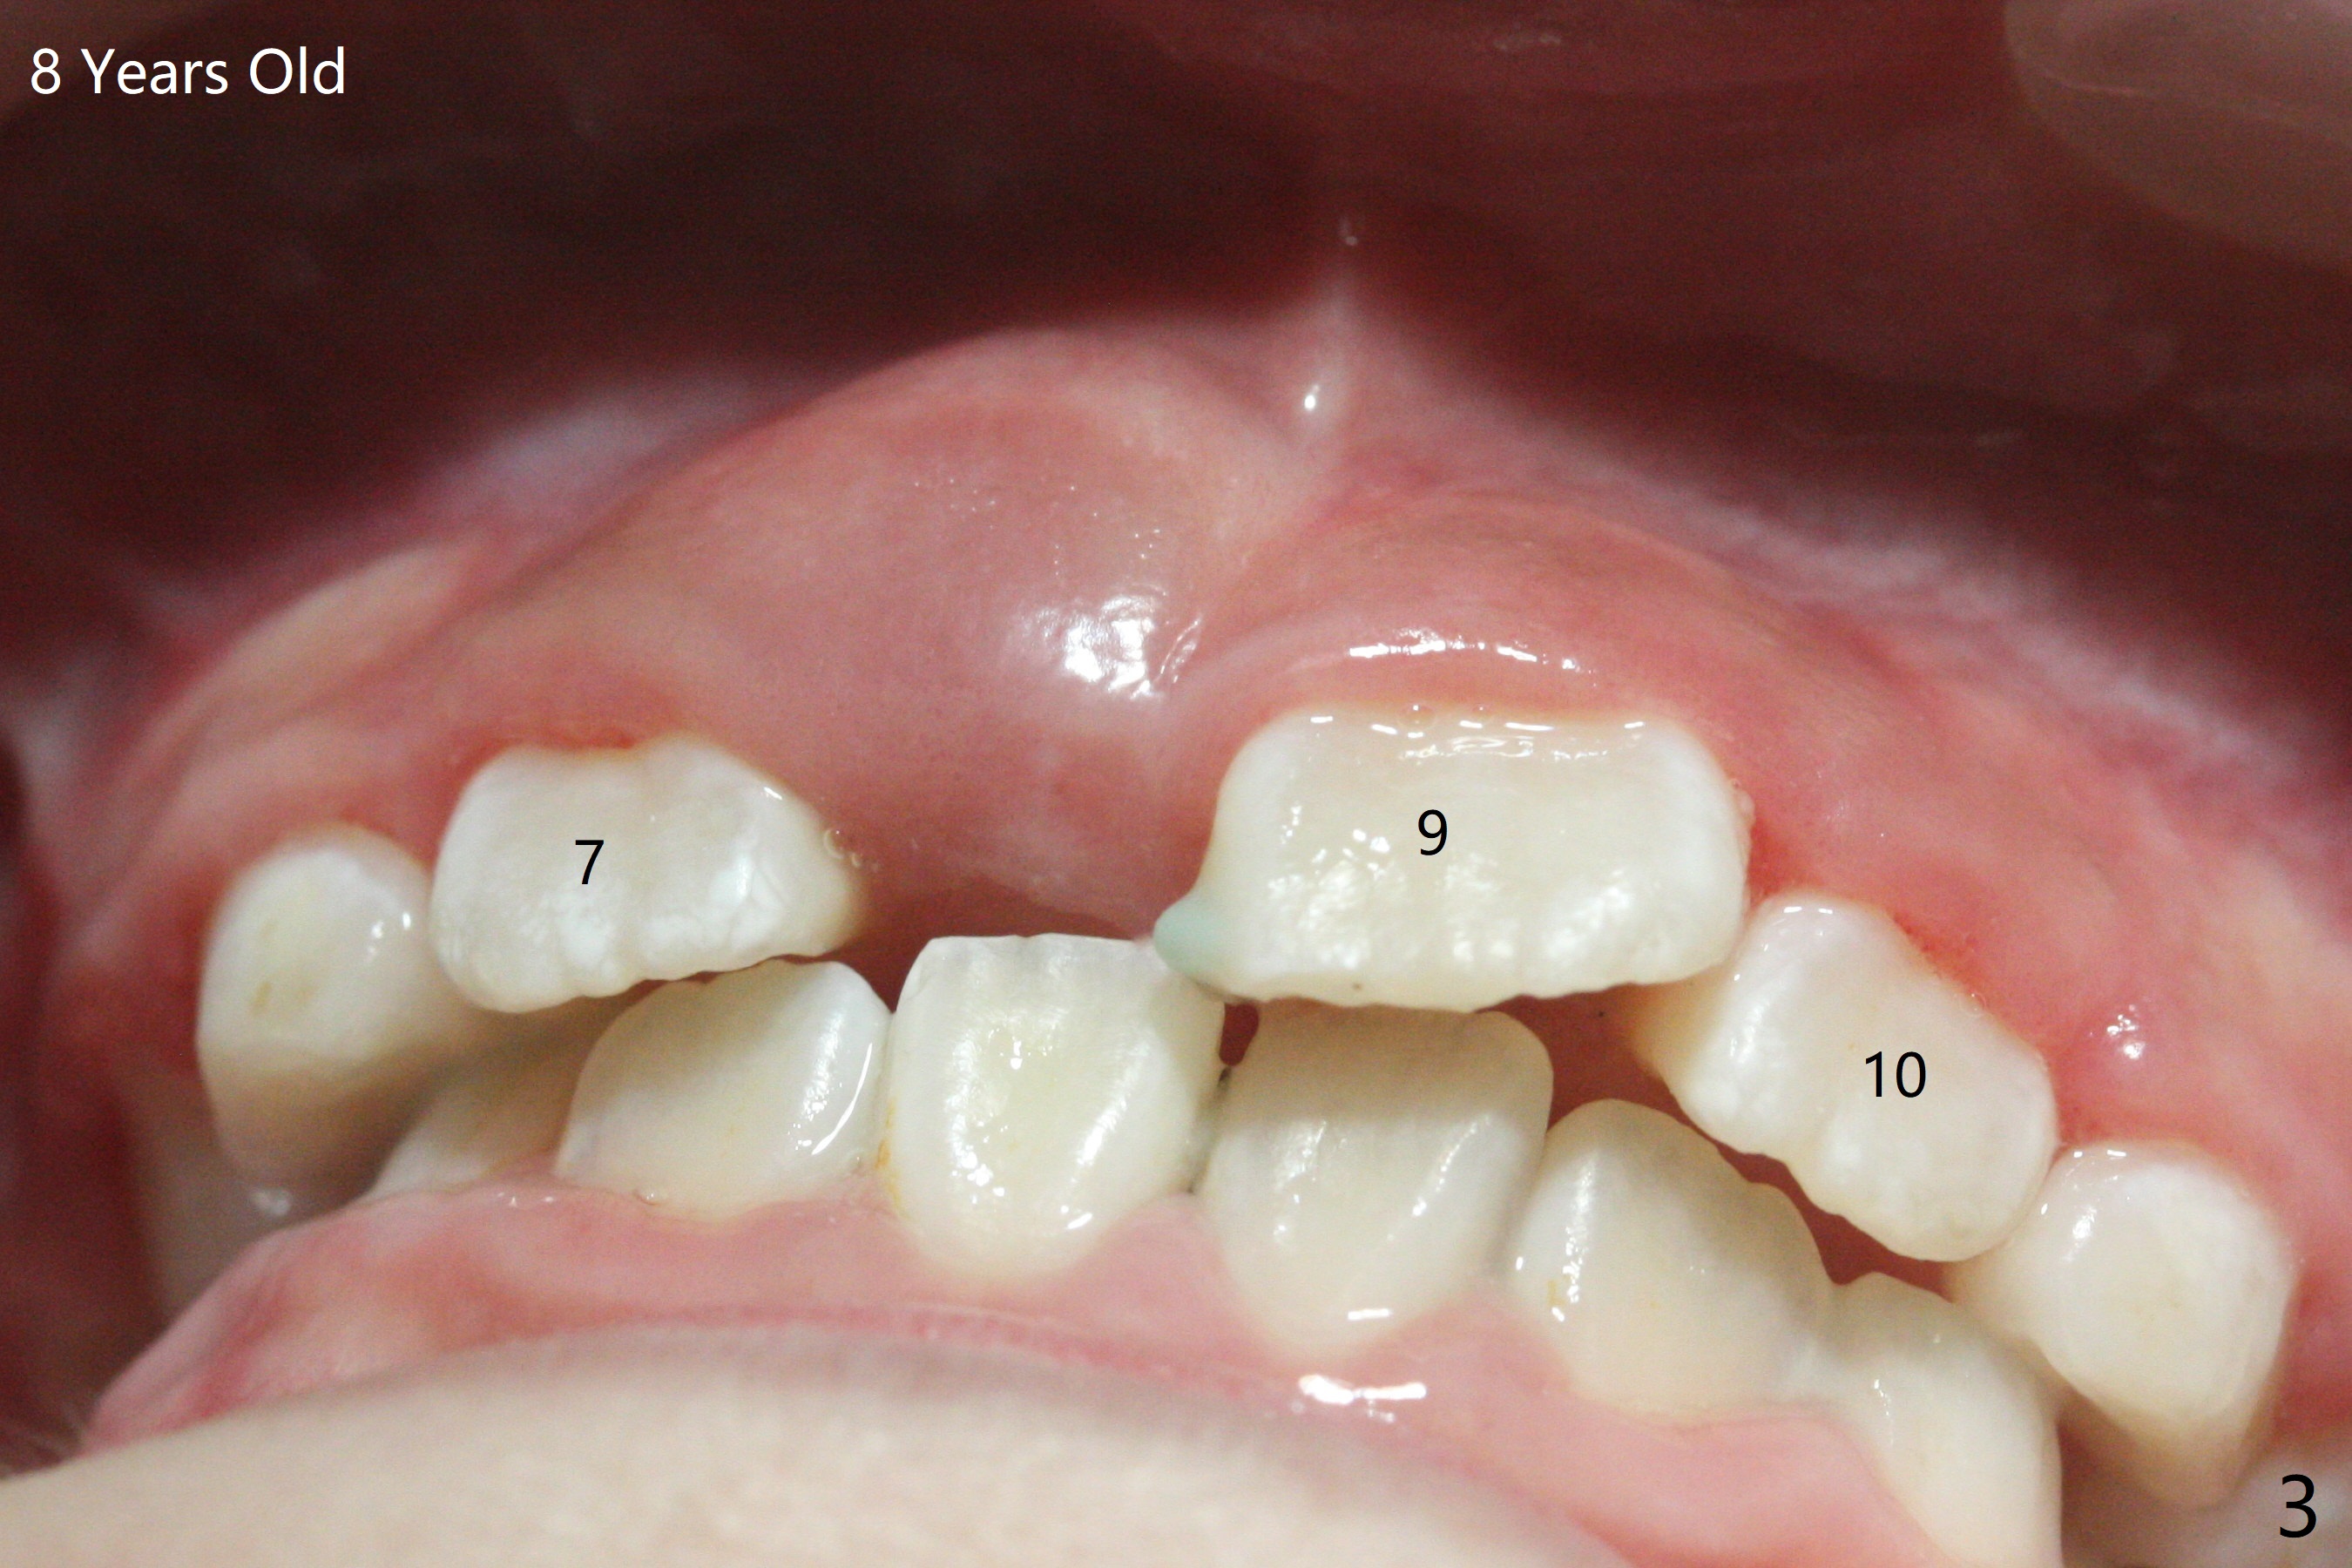

6岁女孩上中切牙发育萌出好像比侧切牙晚(图一),七岁时萌出顺序正常(图二),但是八岁时右上中切牙阻生(图三,四)。似乎拥挤是阻生原因,除了切开助萌之外,扩弓是必要的。不过她口腔卫生欠佳。